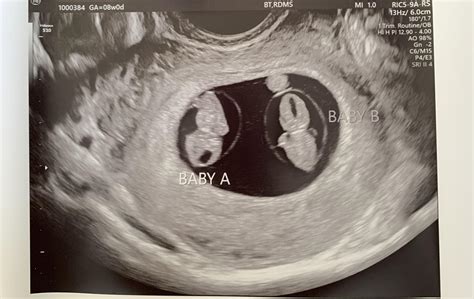

• Multiple Pregnancies: If there is a possibility of carrying multiples, the ultrasound can help confirm the number of fetuses.